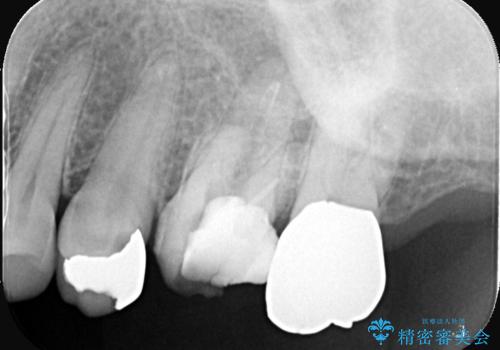

他院で治らなかった根管治療を精密治療で改善|MB2を発見し再治療

- 患者様は、他院で根管治療を受けていたが、なかなか治らず、より精密な治療を希望して当院を受診されました。マイクロスコープを使用して詳しく診断したところ、上顎第一大臼歯(6番)のMB2(第二頬側根管)の見落としが判明。このままでは感染が残り、再発のリスクが高い状態であるため、当院で精密根管治療を行う方針としました。

マイクロスコープを使用してMB2を確認し、感染源を徹底的に除去。その後、根管内を清掃・消毒し、高品質な充填材で密閉しました。従来の根管治療では見落とされがちなMB2の発見により、治療の精度が大幅に向上し、炎症の改善が期待できる状態となりました。患者様からは「治療後の違和感がなくなり、しっかり噛めるようになった」と喜びの声をいただきました。